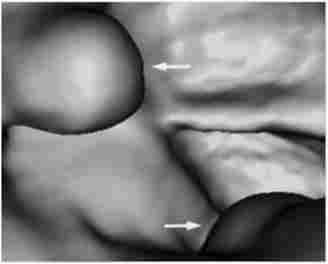

Мал. 14.1. Іригоскопія.

Дефект наповнення при поліпи товстої кишки

Залежно від клінічної ситуації підготовка може бути проведена або шляхом прийому проносних, або очисними клізмами. Пацієнтам, які страждають запорами, рекомендується за 2-3 діб до процедури перейти на бесшлаковую дієту. При проведенні рентгенологічного дослідження (іррігоско- ПІІ) використовують методики тугого і напів тугого заповнення кишечника контрастом; також застосовують метод подвійного контрастування - роздування повітрям заповненої контрастом кишки. Як контрастної речовини використовується сульфат барію. Рентгенологічні ознаки поліпів кишечника - наявність чітких округлих дефектів наповнення (рис. 14.1).

Дане дослідження дозволяє виявити поліпи діаметром до 3-4 мм. При малігнізації новоутворень з'являються ознаки «із'еденно- сти» контурів, можливо наявність стійкого барієвого депо, ригідність і втягнути стінки кишки.